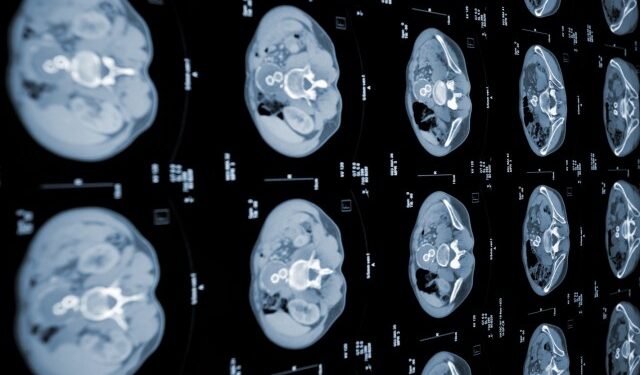

La plataforma, llamada PANDA, es un sistema de aprendizaje profundo que puede identificar características patológicas en imágenes de tomografía que son difíciles de detectar a simple vista, informó hoy la agencia oficial Xinhua.

El modelo se validó más adelante en experimentos en los que participaron 5.337 pacientes de China y la República Checa utilizando escáneres abdominales tomográficos, en los que mostró una sensibilidad y una especificidad del 93,3 % y del 98,8 %, respectivamente, superando el rendimiento de un radiólogo promedio.